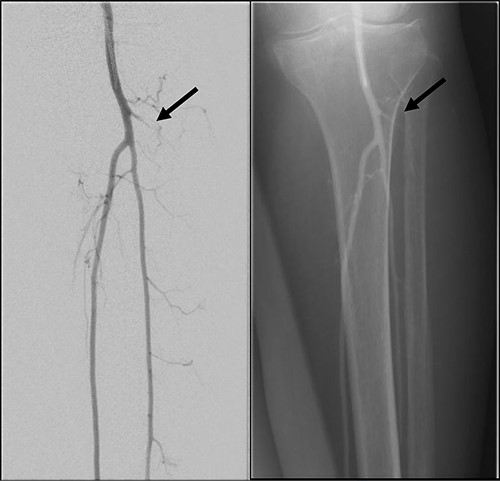

Mdm. S.N.C is a 59-year-old lady with a background of hypertension and diabetes mellitus who had corrective surgery for her left hallux valgus deformity in July 2020 (Fig. 1). This was complicated by wound dehiscence and exposure of the underlying tendon (Extensor hallucis longus) and implant (Fig. 2). An arterial duplex scan was done, which showed 70–80% occlusive disease over the proximal anterior tibial artery (ATA; Fig. 3) that likely contributed to her poor wound healing.

Left lower limb diagnostic angiogram showing occlusion of the ATA with poor flow (arrow).

Angiogram of left distal leg and foot showing poor flow of the distal ATA and dorsalis pedis artery (arrow).